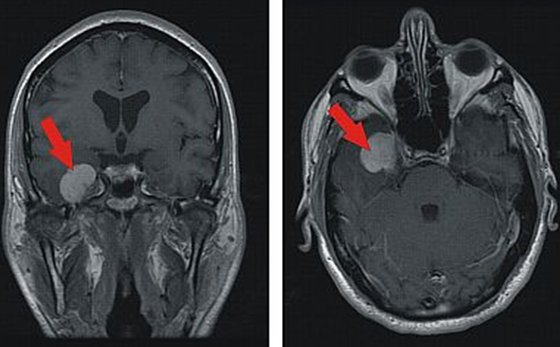

Das Meningeom ist ein meistens gutartiger Tumor der Hirnhaut.

Von den Häuten Meningen des Gehirns oder des Rückenmarks ausgehende Tumore bezeichnet man als Meningeome Hirnhauttumoren. Die Schutzfolien die das Gehirn und das Rückenmark sind Häute bezeichnet. Das Gehirn wird von Schädelknochen umgeben und ist damit der bestgeschützte Teil des Körpers. In diesem steht so quasi als unbedeutenden Nebenbefund folgendes. Das Meningeom ist ein gutartiger Tumor der Hirnhaut der durch die Entartung von Zellen der sogenannten Arachnoidea einer Hirnhautschicht entsteht. Ein menschliches Gehirn aus Silikon. Bösartige Entartungen sind eher selten. Das Gehirn ist umgeben von den Meningen den Hirnhäuten. Meningeom von 13x10x10mm an der ventralen Schädelbasis rechts paramedian.

Die Geschwulst bildet sich vor allem bei Frauen um die 50 Jahre herum. Das Meningeom ist ein gutartiger Tumor der Hirnhaut der durch die Entartung von Zellen der sogenannten Arachnoidea einer Hirnhautschicht entsteht. Wenn Symptome auftreten muss aber in der Regel operiert werden teils. Meningeom von 13x10x10mm an der ventralen Schädelbasis rechts paramedian. In seltenen Fällen kann sich ein gutartiges in ein bösartiges Meningeom umwandeln. Ein menschliches Gehirn aus Silikon. Das ist der einzige Hinweis den habe ich auch nur deshalb erfahren weil ich den Arztbrief gelesen habe.